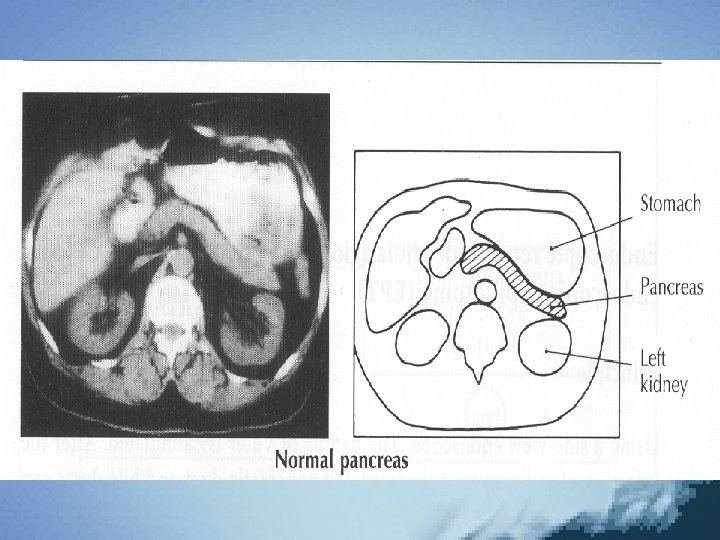

Radyografik çalışmalar • Düz karın grafisi Sentinel lup belirtisi Cut-off belirtisi • PA Akc grafisi Plevral effüzyon • Ultrasonografi Hastaların %50’sinde bulunabilen paralitik ileus nedeniyle optimal inceleme yapılamayabilir • Bilgisayarlı tomografi Dinamik tomografi • ERCP Etyolojinin belirlenmesi EST (endoskopik sfinkterotomi)